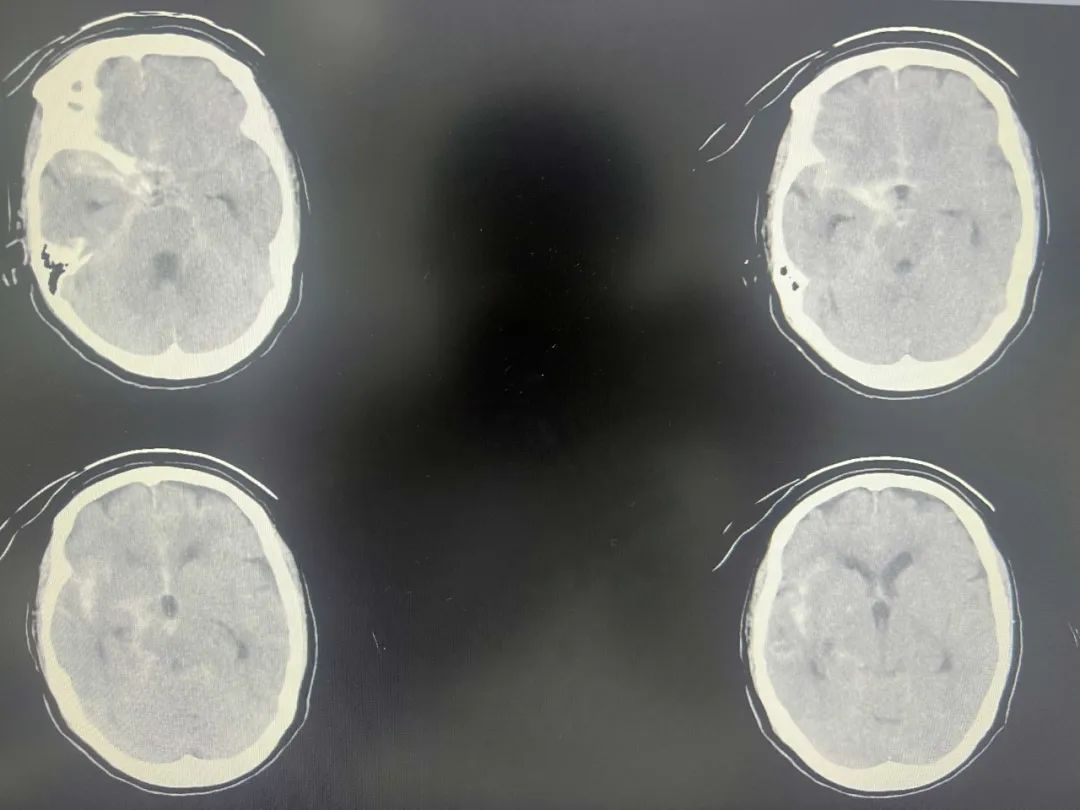

钟阿婆因突发头晕于外院就诊,头颅CT提示蛛网膜下腔出血,转至我院后确诊为颅内动脉瘤破裂出血合并急性心肌梗死(左心室射血分数仅35.4%)。心脑疾病并存导致手术风险极高,家属曾转诊至广州市省级医院,亦被告知急诊手术死亡风险巨大。经慎重考虑,家属决定将患者转回我院ICU。然而治疗初期病情再度恶化,相继出现肺部感染、急性多发性脑梗死及下肢深静脉血栓形成,生命岌岌可危。

▲颅脑CT示蛛网膜下腔出血、